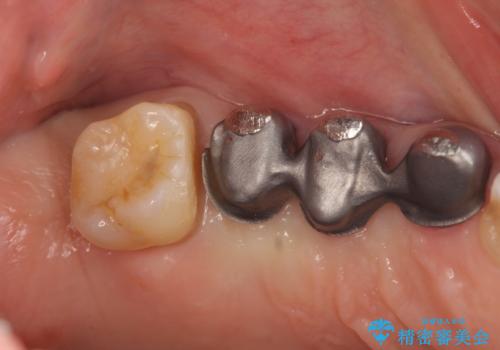

部分矯正を含む 歯周病治療 (再生治療・歯周ポケット除去・MTM・連結補綴)

検査の結果、強い歯ぎしりによる歯の周囲の骨の吸収が認められたため歯槽骨の再生・歯周ポケットの除去・力に対抗する連結補綴・補綴前処置としての小矯正を計画します。

特定の歯に強く力がかかりまた歯周病により臨床歯根が短くなっているような場合、歯の動揺を抑えるため連結補綴が検討されます。

歯の動揺が続くとより周囲の骨を失い最終的には歯を喪失してしまう可能性が高くなってしまうためです。

今回連結補綴を行うにあたり、歯周病の問題を解決するために再生療法・歯周ポケット除去手術を、またより歯の神経を保存し力に対抗できる環境を整えるために小矯正を行い精度の高いメタルボンドクラウンを製作することができました。